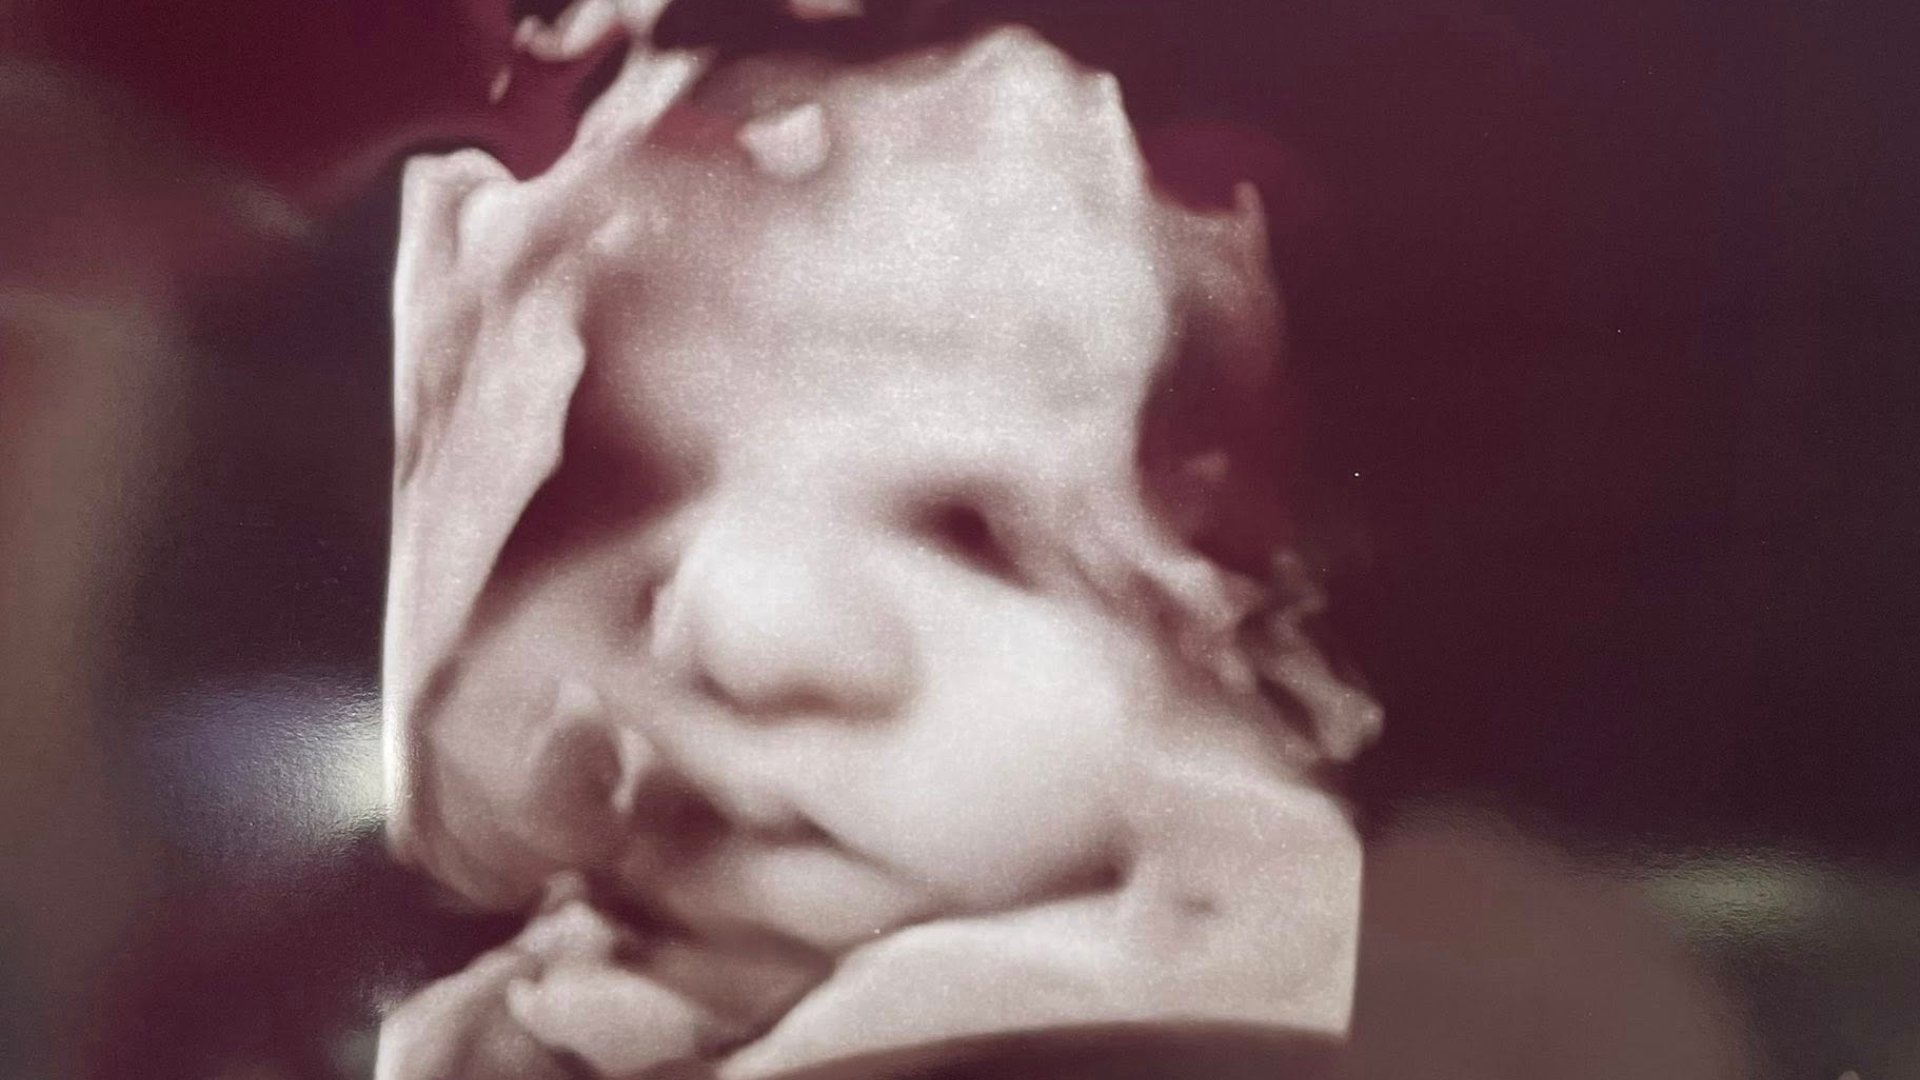

Dua Sonrası Ultrason Görüntüsünde “Tanrı’nın Eli” Göründü: Bebeğin Sağlığı İçin